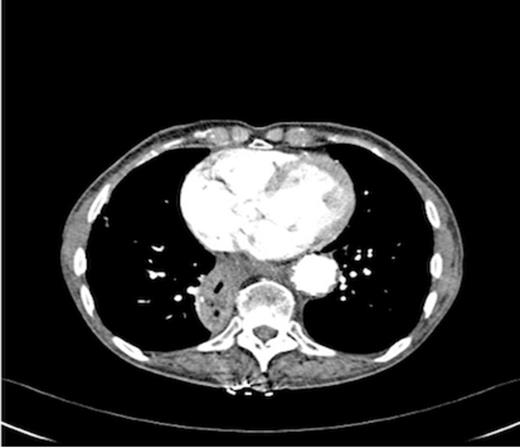

An endoscopy performed four years post-operatively demonstrated two atypical acute gastric ulcers in the distal stomach (figure 1), which were treated with a heat probe (figure 2). Two days later she presented as an emergency in hypovolaemic shock following a large volume haematemesis (haemoglobin of 40g/l). An urgent upper gastrointestinal endoscopy revealed a visible vessel at 35 cm forming part of an expansive mass within the gastric conduit. EUS demonstrated a heterogeneous mass indenting the gastric conduit, containing a strong Doppler signal (figure 3). An urgent computerised tomography (CT) angiogram revealed a Type-A thoracic aortic aneurysm with an enteric fistula (figure 4). The saccular aneurysm of the thoracic aorta was embedded in the gastric conduit. A 28x16cm Valiant® (Medtronic Ltd, Minneapolis, USA) stent was placed in the descending thoracic aorta with good occlusion of the aneurysm. The patient made an excellent recovery and was discharged on the seventh day post stenting.